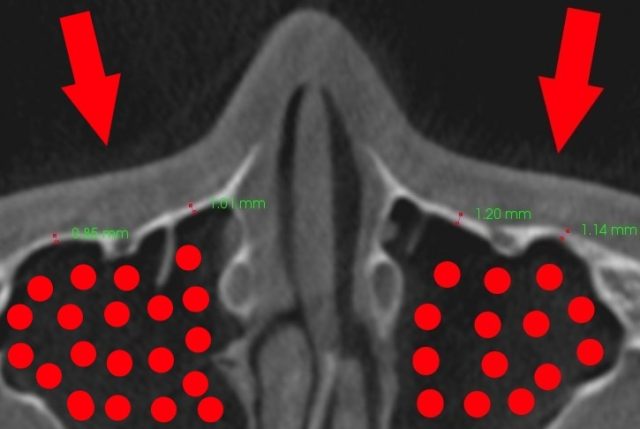

頬骨 押すと痛い 左右両方

頬骨を押すと痛いのは、(赤矢印)

炎症がある上顎洞(赤丸)の

上顎洞の壁(前壁)を

押しているからです。

頬骨を押すと痛いとか、

頬骨を触ると痛くなります。

上図では、

上顎洞前壁の骨の厚みは、

0.9mmから1.2mmです。

炎症は、壁を通り越して、

表の皮膚まで痛くなります。